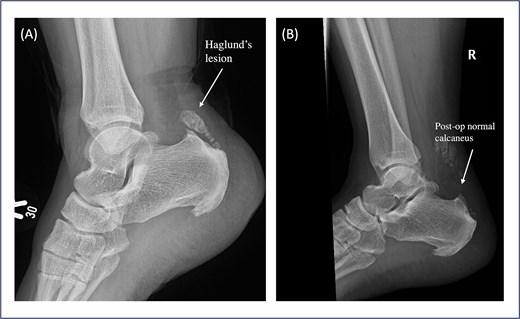

Patient 5 is a 46-year-old female. The patient sustained an ankle twisting injury leading to acute ATR. She has a pre-existing Haglund deformity (Fig. 3A) and developed postoperative calcification near the tendon insertion, which is 6 mm in length. However, no functional limitations or discomfort during dorsiflexion were felt clinically (Fig. 4); this might be a mild complication secondary to local irritation of the tendon or altered healing due to the presence of a bony prominence. She underwent right Achilles tendon repair with flexor hallucis longus (FHL) transport and Y lengthening. She began weight-bearing at 3 weeks following the same protocol as other patients. However, at the final follow up the patient had not yet returned to sports and reported an ATRS score of 75, the lowest amongst the patients in the series. This indicates that there are ongoing limitations in function or confidence. Whilst the patient’s surgical and post-operative course was uneventful, this may reflect delayed tendon remodelling, reduced strength, pain or psychosocial factors such as fear of re-injury.

Pre- and postoperative lateral ankle X-ray of Patient 5. (A) Pre-operative shows a prominent Haglund’s lesion before surgery. (B) The postoperative image demonstrates a normalized calcaneal contour following debridement and Achilles tendon repair, suggesting adequate resection and restoration of the tendon insertion profile.